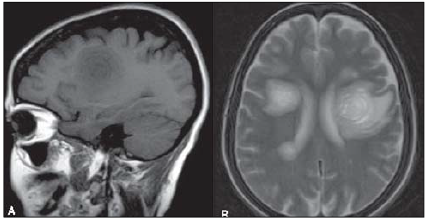

Avalie o seguinte achado radiográfico de uma ressonância magnética, plano sagital ponderada em T1 (A) e axial ponderada em T2 (B). enunciado 974415-1 (Disponível em: http://www.rb.org.br/imagens/v44n2a13-fig11.jpg.)

O achado radiográfico trata-se de: